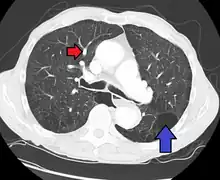

CT scan

Signs of pulmonary hypertension on CT scan of the chest are:

- Enlargement of the pulmonary trunk (measured at its bifurcation). It is, however, a poor predictor of pulmonary hypertension in patients with interstitial lung disease.[62]

- A diameter of more than 27 mm for women and 29 mm for men is suggested as a cutoff.[62]

- A cutoff of 31.6 mm may be a more statistically robust in individuals without interstitial lung disease.[62]

- Increased ratio of the diameter of the main pulmonary artery (pulmonary trunk) to the ascending aorta (measured at its bifurcation).

- Increased diameter ratio of segmental arteries to bronchi. This finding in three or four lobes, in the presence of a dilated pulmonary trunk (≥29 mm), and absence of significant structural lung disease confers a specificity of 100% for pulmonary hypertension.[62]

- Mural calcification in central pulmonary arteries is most frequently seen in patients with Eisenmenger's syndrome.[62]